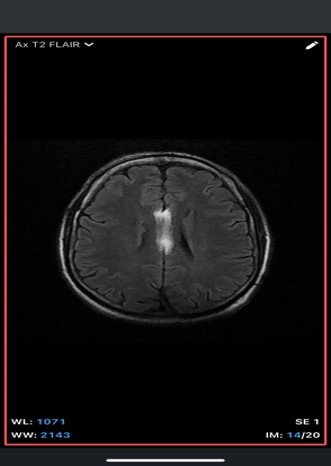

An extra-axial TI/T/Flair hyperintense lesion in midline at the inferior edge of the interhemispherie fissure extending along the superior margins of the corpus callosum with areas of blooming consistent with calcification and no post contrast enhancement –likely pericallosal lipoma.

• MRI

• T1-weighted: Hyperintense (fat signal).

• T2-weighted: Variable, usually hyperintense; may show chemical shift artifacts.

• Fat-suppressed sequences: Complete signal suppression confirms fat composition.

• Post-contrast: No enhancement.